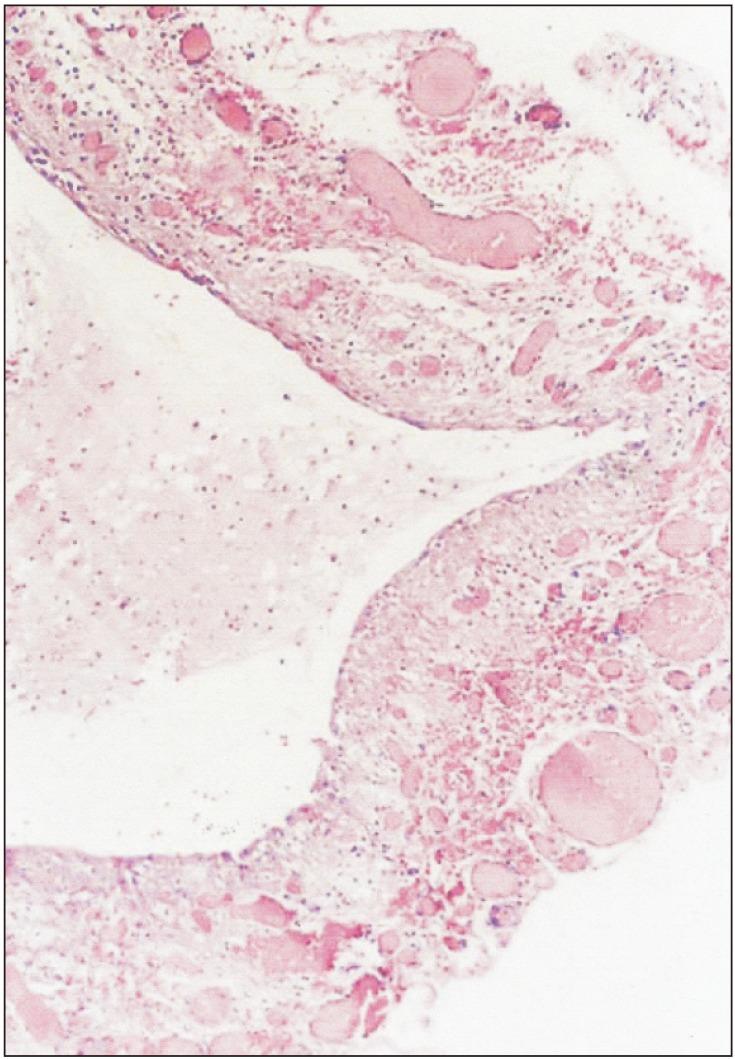

Ranula is a mucocele caused by extravasation of the sublingual gland on the floor of the mouth. The most common presentation is a cystic mass in the floor of the mouth. A portion of the sublingual gland could herniate through the mylohyoid muscle, and its extravasated mucin can spread along this hiatus into submandibular and submental spaces and cause cervical swelling. This phenomenon is called plunging ranula. A variety of treatments for ranula has been suggested and include aspiration of cystic fluid, sclerotherapy, marsupialization, incision and drainage, ranula excision only, and excision of the sublingual gland with or without ranula. Those various treatments have shown diverse results. Most surgeons agree that removal of the sublingual gland is necessary in oral and plunging ranula. Four patients with ranula were investigated retrospectively, and treatment methods based on literature review were attempted.

舌下囊肿是由舌下腺在口腔底部外渗引起的黏液囊肿。最常见的表现是口腔底部的囊性肿物。舌下腺的一部分可通过下颌舌骨肌疝出,其外渗的黏液可沿此裂隙扩散至颌下间隙和颏下间隙,导致颈部肿胀。这种现象称为舌下囊肿脱垂。已经提出了多种治疗舌下囊肿的方法,包括抽吸囊液、硬化疗法、袋形缝合术、切开引流、仅切除舌下囊肿以及切除舌下腺(伴或不伴舌下囊肿)。这些不同的治疗方法显示出了不同的结果。大多数外科医生一致认为,对于口腔内和脱垂性舌下囊肿,切除舌下腺是必要的。对4例舌下囊肿患者进行了回顾性研究,并尝试了基于文献综述的治疗方法。